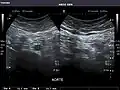

Aorta: Visualized portions normal in caliber, 16 x 15 mm.

Aorta -